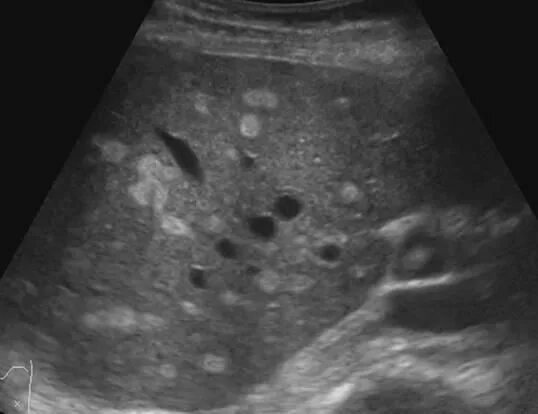

Белое пятно на узи